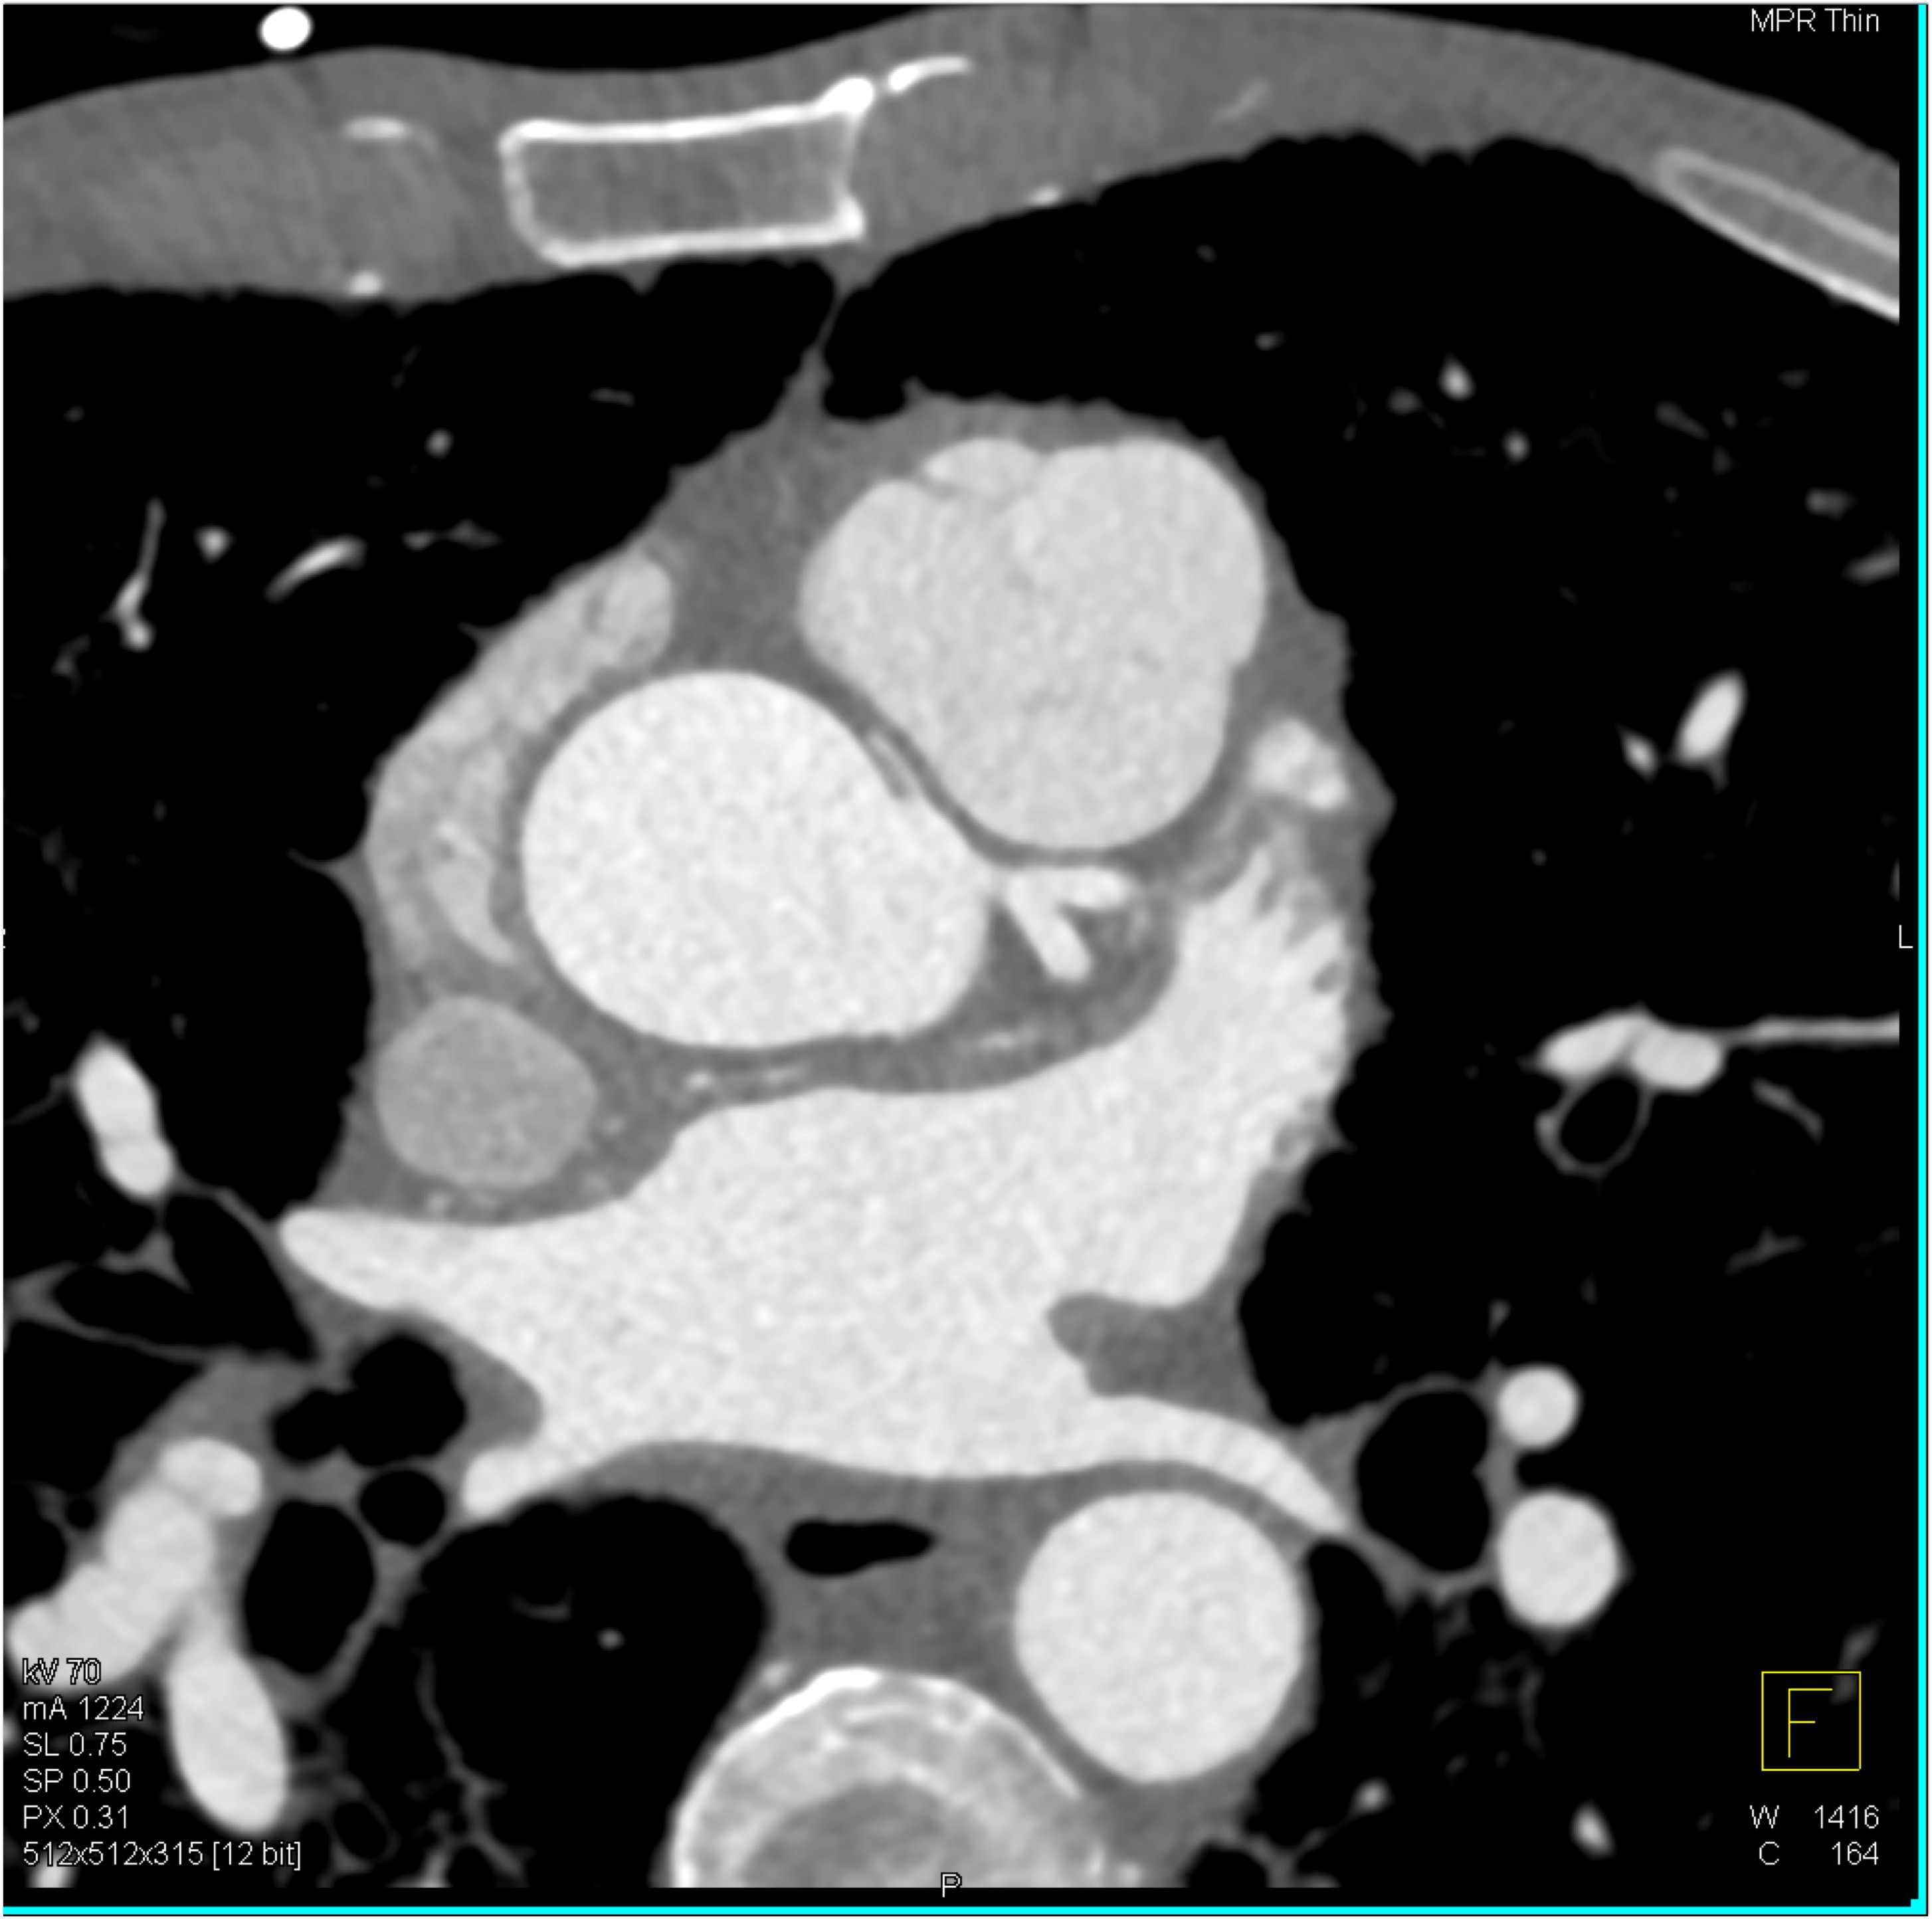

9) The key finding on this coronary CTA in this patient with chest pain is?

LAD occlusion

LAD stenosis

RCA occlusion

RCA arises off the left cusp